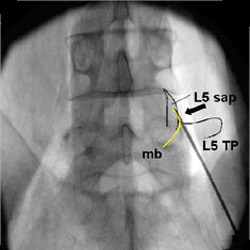

Wenn bei diesen Schmerzen die diagnostischen und therapeutisch eingesetzten Injektionen mit abschwellenden oder Knorpel aufbauenden Substanzen nicht mehr ausreichen, führt man eine Radiofrequenztherapie (Thermokoagulation) durch. Dabei werden die rein sensiblen Nervenästchen verödet, um langfristig eine Beschwerdelinderung zu erreichen. Die Radiofrequenztherapie ist hierfür der am besten geprüfte und wissenschaftlich als am wirksamsten bewiesene schmerztherapeutische Eingriff.